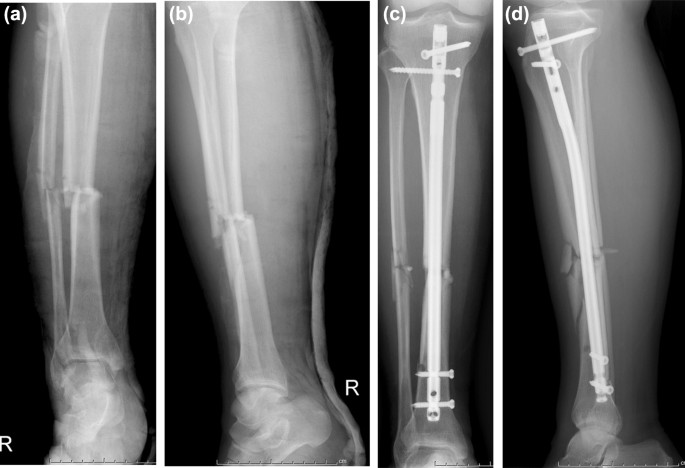

Un clou centromédullaire tibial est un dispositif médical conçu pour stabiliser et favoriser la cicatrisation des fractures de la diaphyse tibiale.Il se compose d'une tige métallique insérée dans le centre creux de l'os, offrant stabilité et soutien pendant le processus de guérison.Le clou est généralement en titane ou en acier inoxydable et est disponible en différentes tailles pour s'adapter aux différentes anatomies des patients.

Les clous centromédullaires tibiaux sont couramment utilisés pour le traitement des fractures de la diaphyse tibiale.Ils sont particulièrement efficaces pour les fractures nécessitant une fixation stable, telles que les fractures déplacées ou comminutives.Cette technique convient également aux cas de mauvaise qualité osseuse ou lorsqu'une mise en charge immédiate est souhaitée.

Après avoir créé un point d'entrée dans le tibia proximal, le chirurgien insère avec précaution le clou intramédullaire tibial dans le canal médullaire.Un guidage fluoroscopique est utilisé pour assurer un placement et un alignement précis.Le clou est avancé à travers l'os, réalignant tous les fragments déplacés et rétablissant l'alignement anatomique approprié.

Une fois le clou correctement positionné, des vis de verrouillage sont insérées pour fixer le clou dans l'os.Ces vis offrent une stabilité supplémentaire et empêchent les mouvements de rotation ou axiaux des fragments de fracture.Le nombre et le placement des vis dépendent du type de fracture et de la préférence du chirurgien.

De nombreux patients ont connu des résultats positifs avec la chirurgie du clou intramédullaire tibial.Une étude de cas concernait une personne de 35 ans avec une fracture comminutive de la diaphyse tibiale.Après avoir subi une intervention chirurgicale avec un clou intramédullaire tibial, le patient a obtenu une consolidation solide de la fracture, a retrouvé sa pleine capacité portante et est revenu à son niveau d'activité antérieur dans les six mois.